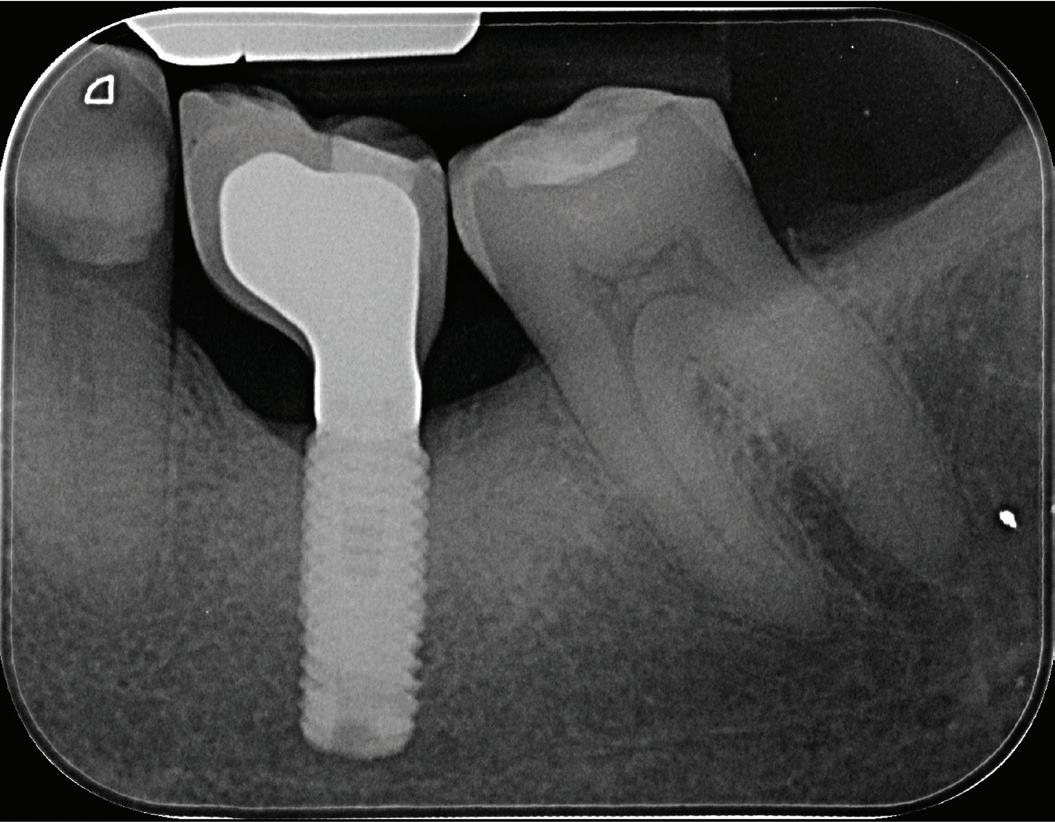

A 55-year-old woman presented for diagnosis of pain in the maxillary left posterior quadrant. About 1 year prior to that date, another endodontist had performed endodontic therapy on tooth 15. She had continued symptoms in the area. The endodontist checked tooth 15 and did not believe that her symptoms were related to that tooth, but he did not diagnose the source of her symptoms. On the day of my consultation, if she pushed laterally on tooth 15 with her tongue, she could elicit moderately sharp pain. She also had a constant ache in the area.

A periapical radiograph and a limitedfield-of-view cone beam computed tomogram of teeth 14 and 15 were taken, and no radiographic signs of apical periodontitis related to these teeth were noted that day (Fig 1). Sensibility tests were also performed. Tooth 15 responded normally to palpation and to bite and felt “different” on percussion (not painful, which is an important distinction to make). Tooth 14 responded

normally to palpation, percussion, and bite. Cold placed on tooth 14 triggered a significantly elevated, throbbing response that lingered more than 1 minute. Of all the tests performed, the cold on tooth 14 most closely replicated the pain of her chief complaint.

We reviewed treatment options, including no treatment. She elected to have endodontic therapy on tooth 14 performed that day. Local anesthetic was administered, and a dental dam was placed. This molar was slightly unusual in that I obtained patency in the palatal, distobuccal, and second mesiobuccal canals (MB2) that day, but the first mesiobuccal canal (MB1) was still not patent. Usually, it is MB2 that is the hardest to instrument. Calcium hydroxide medicament and a provisional restoration were placed. The patient was scheduled to return in 2 weeks for completion of endodontic therapy on tooth 14.

When she returned, I asked about her symptoms. The overall pain had reduced significantly, and the pain in tooth 15 with lateral pressure was gone, but there was still a deep ache in the area, now focused near tooth 15. She noticed a throbbing in the area with positional changes, such as sitting up and bending over. Sensibility tests were performed again. Tooth 14 responded normally to percussion, palpation, and bite. Tooth 15 responded normally to palpation, and percussion and bite elicited a moderately painful response (different from the results of the sensibility

tests performed preoperatively). We discussed the possible reasons for the pathosis related to tooth 15, including fracture. I recommended that if she desired to save the tooth, we should initiate retreatment of tooth 15 and place calcium hydroxide in the tooth. I would then see her a month later for a short consultation to check on her symptoms before obturating teeth 14 and 15. She agreed to this treatment plan.

Orthograde retreatment of tooth 15 was initiated that day in the usual manner, and calcium hydroxide was placed. At the follow-up appointment 1 month later, she was happy to report that

all her symptoms had resolved and that she had not needed to take ibuprofen or acetaminophen for more than 2 weeks. Both teeth were tested that day, and both responded normally to percussion, palpation, and bite. We then scheduled her for completion of treatment of both teeth.

At our final appointment, I was able to fully instrument the MB1 canal. The final postoperative radiograph shows the curvature of the MB1 canal of tooth 14 (Fig 2). The teeth were closed with a medicated sponge and provisional material, and the patient was referred back to her general dentist for restoration of these teeth.

Fig 2. Postoperative radiograph of teeth 14 and 15.

Fig 1. Preoperative radiographs. A. Tooth 14. B. Tooth 15.